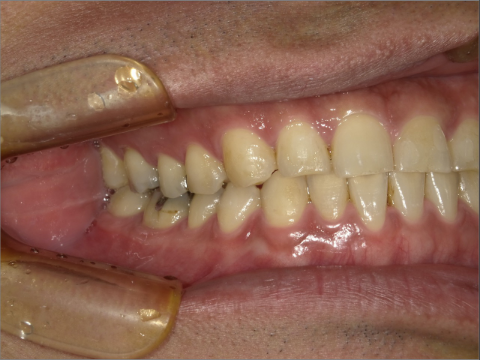

ご年齢 35歳男性

治療期間 2022/08/22〜2023/03/24(1年5ヶ月)

診断 110,000円(税込)

アライナー 550,000円(税込)

リテーナー 55,000円(税込)

BEFORE

AFTER